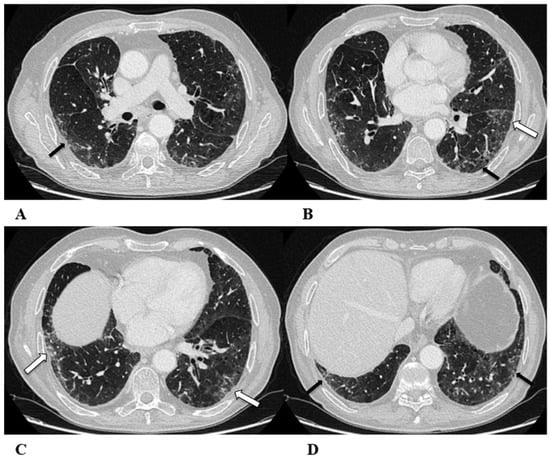

Figure 2.

Non-specific interstitial pneumonia (NSIP). Non-specific interstitial pneumonia represents the second most commonly described pattern of ICI-related pneumonitis. It is defined pathologically by different degrees of interstitial inflammatory cell infiltrates and/or fibrosis. HRCT characteristics in patients with NSIP consist of GGOs associated with irregular reticulations and traction bronchiectasis/bronchiolectasis. Honeycombing is infrequent and minimally represented. NSIP distribution is usually bilateral and symmetric, predominantly subpleural and basal, and often with sparing of the immediate subpleural lung.

The NSIP pattern should be distinguished from atypical pneumonia based on clinical analysis. The greater involvement of the lung bases and recurrent relative subpleural sparing must be considered in the clinical assessment of the patient, as they are uncommon findings in infectious processes. It is also necessary to exclude the concomitance of immune disorders and connective tissue diseases [9,12].

(A–D) A 70-year-old man with lung adenocarcinoma and brain metastases treated with pembrolizumab, carboplatin and pemetrexed as first-line treatment. Two months later, the patient had dyspnea and dry cough, without fever.

Axial chest CT scans show mild subpleural reticulation in the lower lobes (black arrows (A,B,D)) and patchy bilateral and partially confluent areas of GGO in both lungs predominant in the lower lobes (white arrows (B,C)). Incidental findings: rare small lucent areas of centrilobular emphysema, especially in both upper lobes.